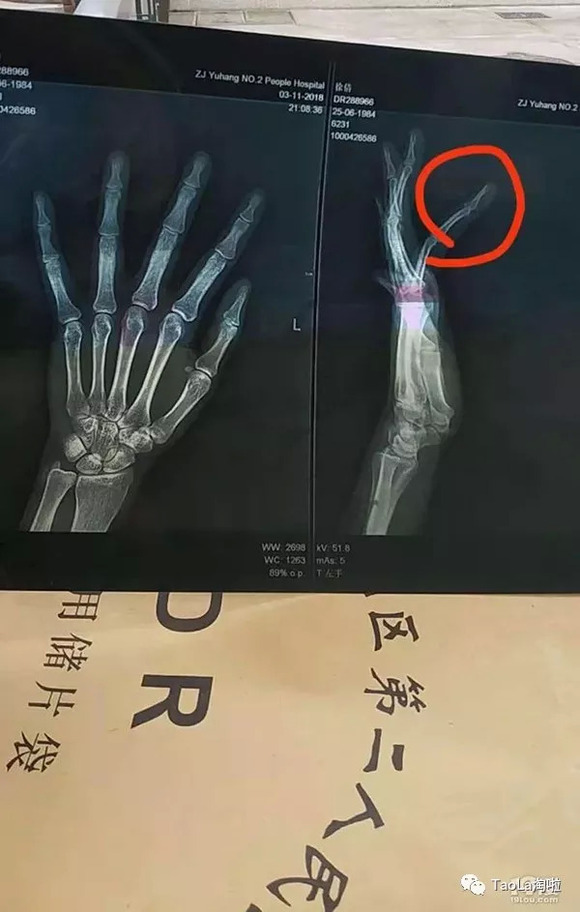

事后,徐女士报了警,民警迅速赶到现场了解情况。徐女士当晚到医院检查发现手指骨折,身上还有多处挫伤。